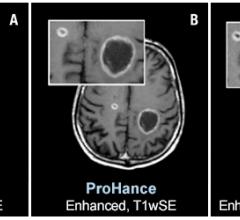

Bracco Diagnostics Inc. announced the labeling of its contrast agent MultiHance has obtained U.S. Food and Drug Administration (FDA) approval for an extension to include magnetic resonance imaging (MRI) of the central nervous system (CNS) in pediatric patients younger than 2 years of age (including term neonates). The agent may now be used in this patient population to visualize lesions with abnormal blood-brain barrier or abnormal vascularity of the brain, spine and associated tissues.